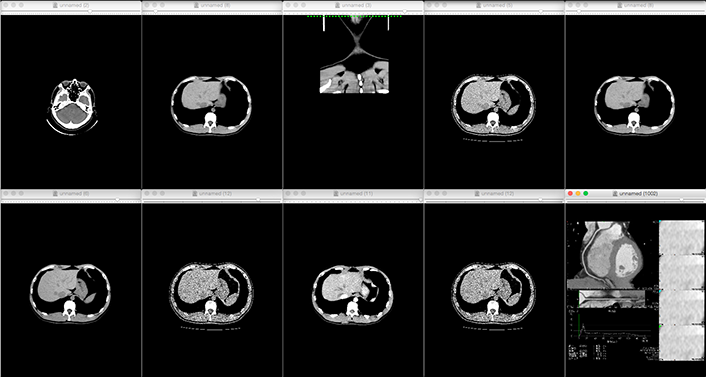

In recent years, the evolution and widespread use of dental CT and medical CT has made it possible to obtain data (dentition and skeletal structure) from patients themselves, and by processing the data obtained from CT imaging and outputting it to a 3D printer, preoperative simulations can now be performed on full-scale models. With a full-scale model in hand, the treatment team can share information about the fit, which is not possible on a CAD screen, and formulate an advanced treatment plan.

Reads DICOM data obtained from CT imaging into mimics

Eliminates noise (artifacts) generated by metal and other materials

We will convert the data into 3D data

and confirm with the customer that the area of interest has been

reproduced in the image or data*If the STL output is available directly from the medical workstation,

the above process is eliminated. -